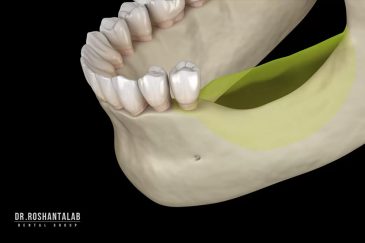

🔸جراحی پیشرفته نظیر سینوس لیفت